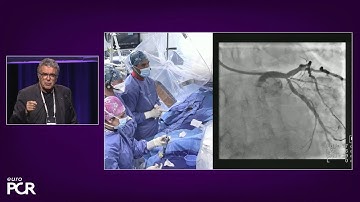

Difficult Radial Anatomy in Coplex PCI